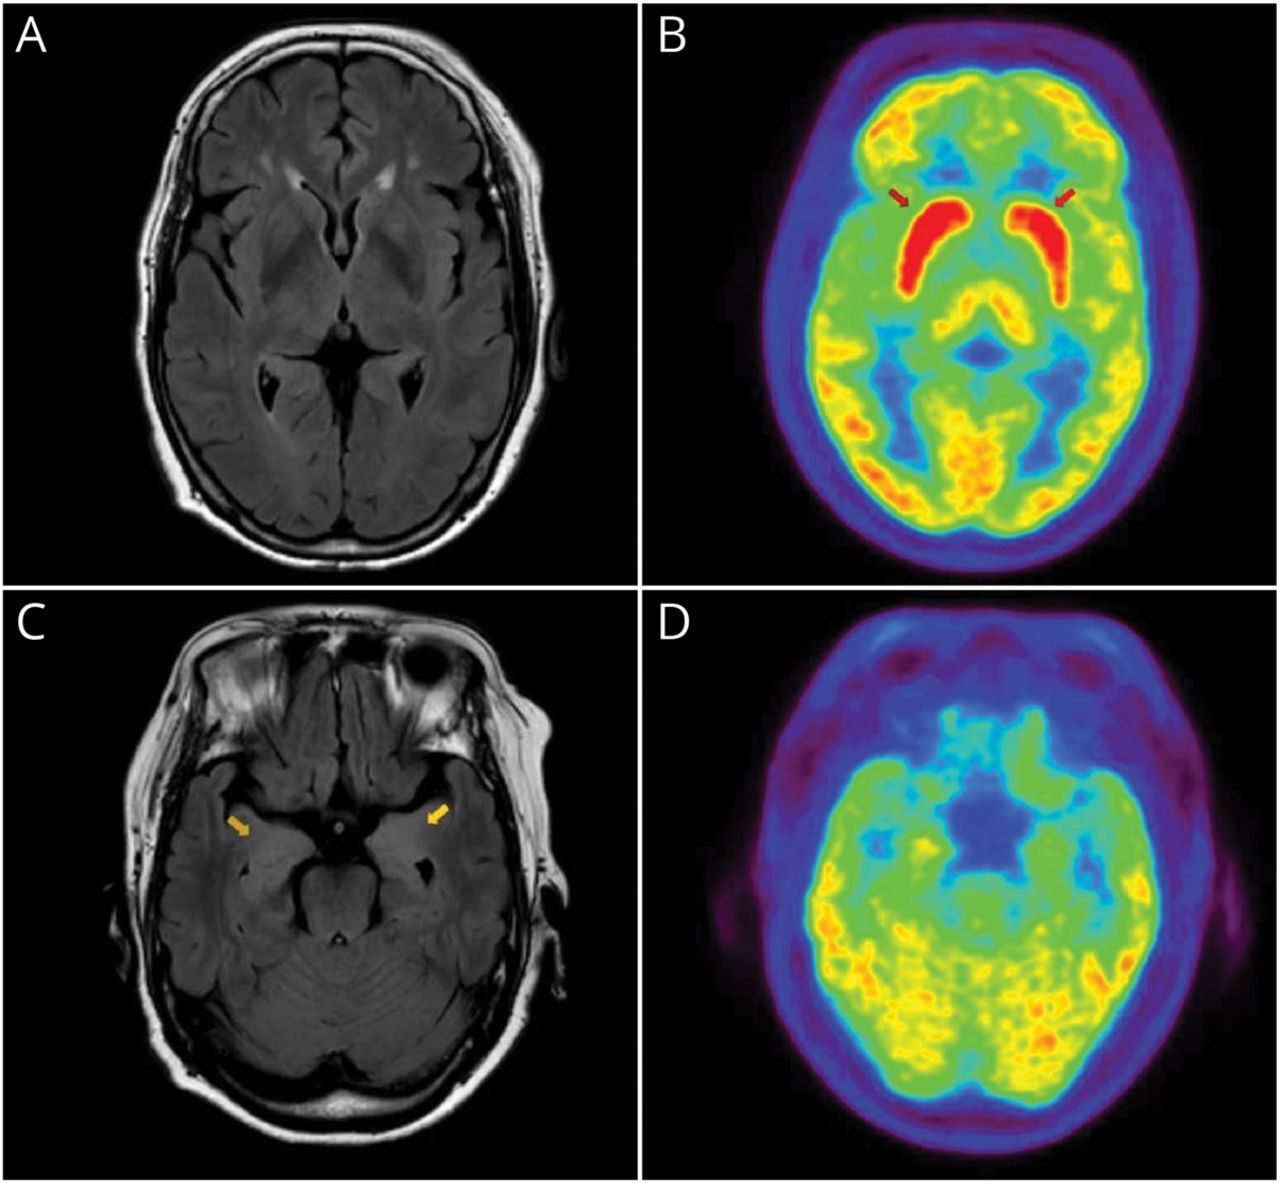

我们与轴向削减显示基底神经节(A和B)和内侧颞叶(C和D) diffusion-weighted成像(驾车)和表观扩散系数(ADC)的MRI序列。没有扩散限制损伤。